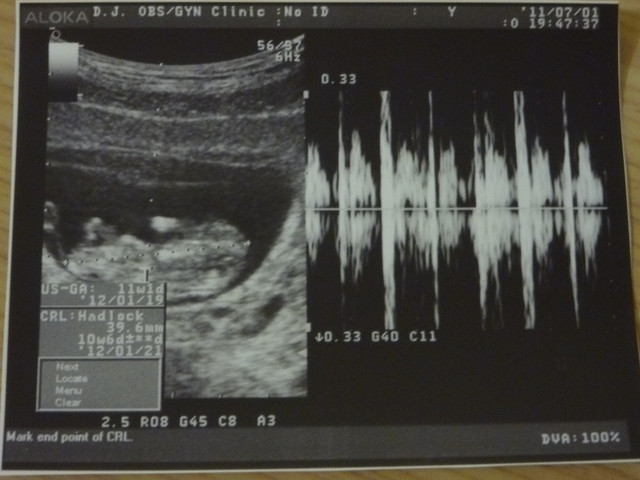

結果照超音波之後

果然胎兒周圍還是有零星出血(胎兒下方零星一塊塊黑黑的就是出血的地方)

今天小寶貝身長3.96cm

今天依小貝果的大小

結果預產期又提前押在2012/01/23

目前大小都正常胎兒狀況也OK!!